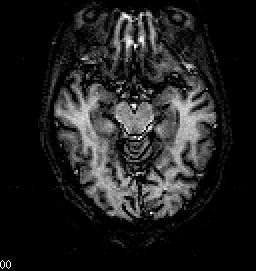

• Horizontal View of Nestor's Brain ,

Approximately 95 mm from the top of the head.